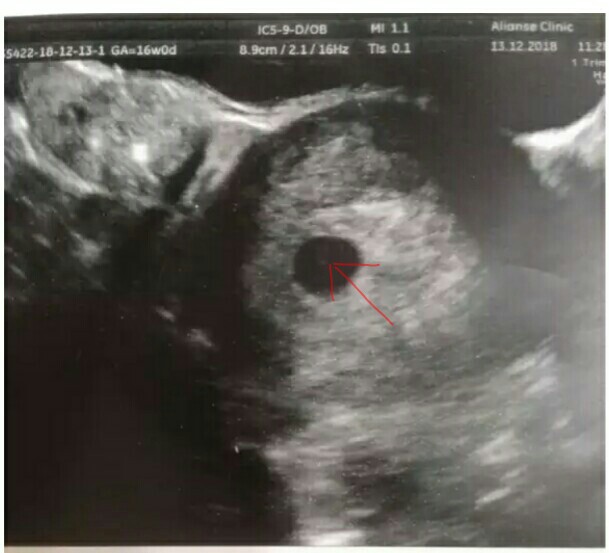

а я на фото вижу эмбрион🤔 червячек такой

вот что-то кругленькое

Может у вас поздняя овуляция? Свд еще маленький для эмбриона, но наличие желточного мешочка говорит о том, что скоро должен появиться. Но! бывают исключения( У меня при 11мм не было, при 20мм увидели

У меня в плодном яйце 20 мм не нашли эмбрион. Нашли через неделю в 28 мм. Ждите 12 недель и идите не скрининг, все нормально